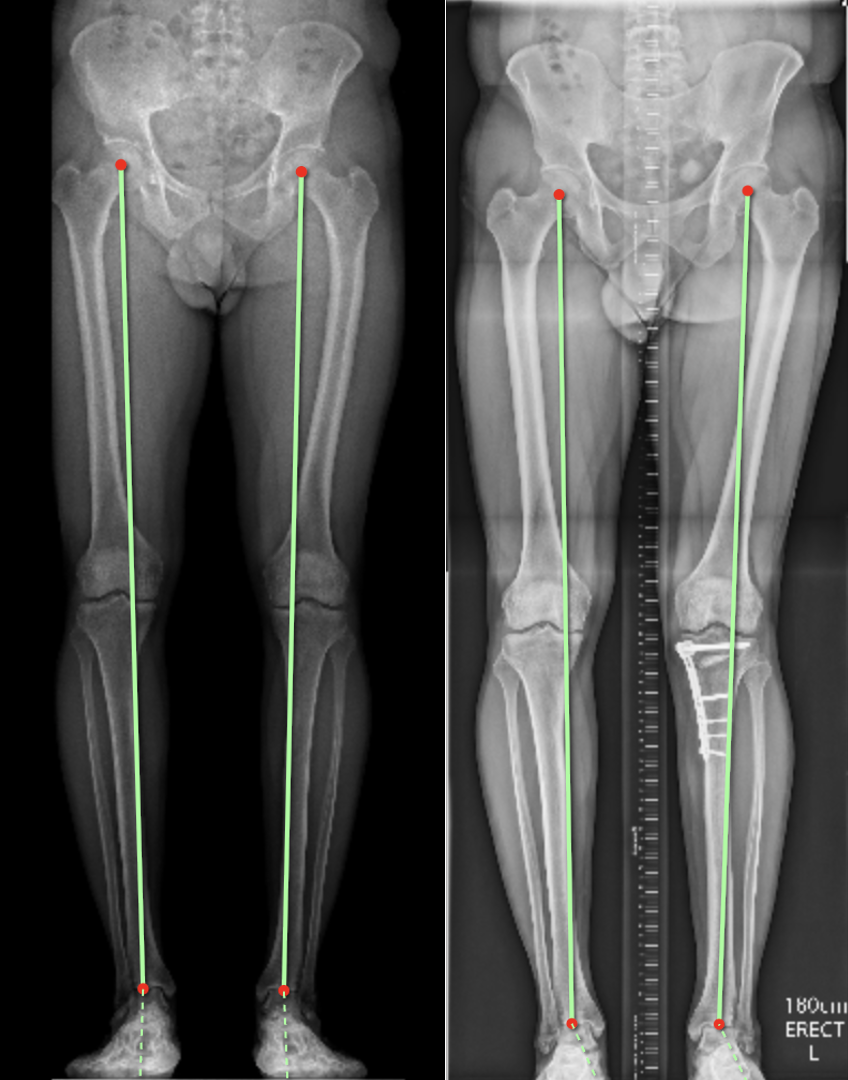

The picture on the left shows the weight-bearing axis passing through the inner (medial joint). The picture on the right is the same patient after surgery. A medial opening wedge high tibial osteotomy was performed with bone grafting. Post-osteotomy the leg is aligned in an appropriately over-corrected valgus (knock-kneed) position and the healthy lateral compartment takes the majority of the load.

A medial opening wedge high-tibial osteotomy with artificial bone graft.